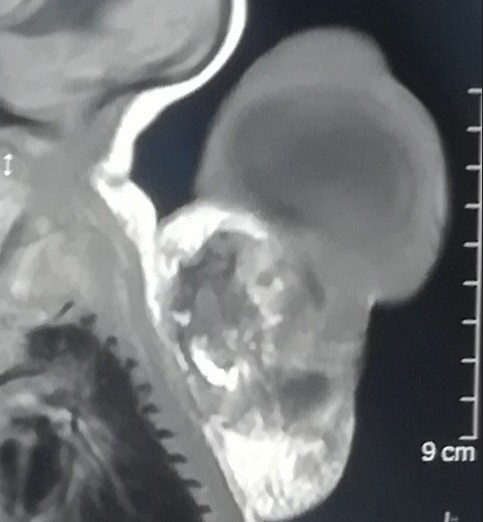

teratoma of the thoracic vertebrae in a newborn